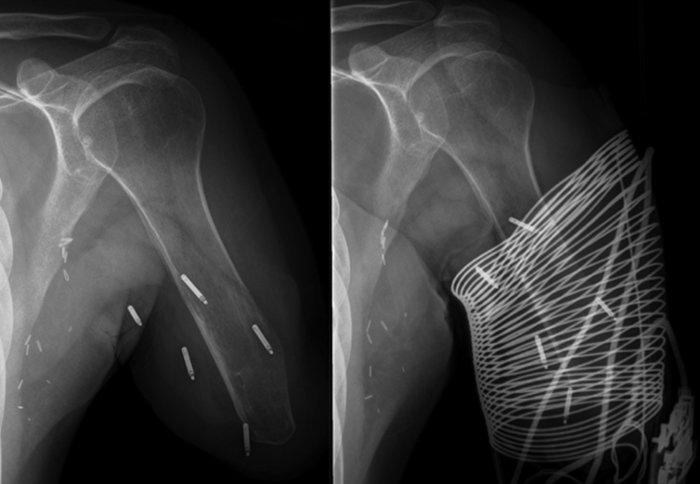

This early-stage research, on three men with above-elbow arm amputations, involved relocating nerves in their remaining arms before implanting wirelessly chargeable electrodes and fitting new prosthetic arms.

In this study, researchers and surgeons at the Vienna and Imperial tested whether implanting electrodes into the stump itself could improve patients’ experience of using prosthetics.

They connected electrodes to nerves and muscles in the stumps to give users more control over movement, and to let the prosthetic ‘feel’ deeper muscles to get a better idea of the precise movements wanted by the user.

Following surgery to relocate nerves to the stump and implant the electrodes, they fitted the prostheses and followed the patients’ progress and their prosthetics’ performance for more than two years. This makes this the first long-term study to combine implantable systems with nerve transfer surgery.